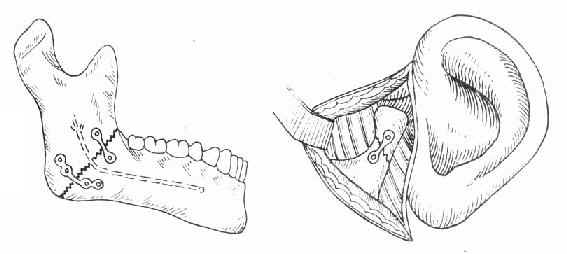

2.牵引复位:颌骨骨折后,经过较长时间(上颌骨三周以上,下颌骨四周以上),骨折处已有部分纤维组织愈合,手法复位不成功,可采用牵引复位法。下颌骨骨折多用颌间牵引,就是在下颌骨有移位的骨折段上安置分段牙弓夹板(图4-16),然后在与上颌的牙弓夹板之间,用小橡皮圈作弹性牵引,使之逐渐恢复正常的咬合关系。上颌骨骨折后,如骨折段向后移位,可在上颌牙列上安置牙弓夹板,在头部制作带有金属支架的石膏帽,在牙弓夹板与金属支架之间作弹性牵引,使上颌骨骨折段向前复位(图 4-17)。需要较大牵引力时,也可作卧式重力性牵引。

| 图4-16 分段式牙弓夹板 | 图4-17 金属支架石膏帽,将上颌骨骨折段向前牵引复 |

4.小钢板或微型钢板固定:在手法切开复位的基础上,将适当长度和适合形态小钢板或微型钢板跨置于骨折两断端的骨面上,用特制的螺钉穿骨皮质固定钢板,达到固定骨折的目的(图4-21)。小钢板一般用于下颌骨,微型钢板适用于上颌骨。

图4-21 小钢板或微型钢板固定法